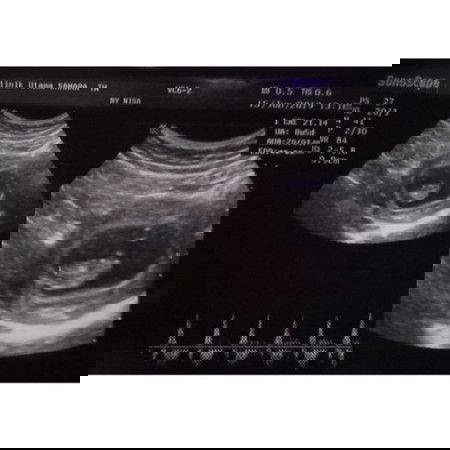

buuun.. ada yg usg nya kaya saya ga ya. ini kemaren usg usia 9/10minggu. detak jantungnya udah kedenger bun. tapi di usg samping janinnya itu item. kata dokter takutnya keguguran, aku disuruh banyakin istirahat buun, bedrest nya berapa lama ya buun..

samping mn ya bund? klo yg lingkar itu cadangan makanan janin ny klo bedrest yg aman itu smp tmt 2,tp tiap org beda2 si bund nanti klo spog blg udh kuat,biasa ny dblg i